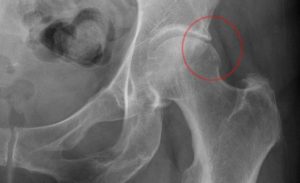

Выделяют два типа фемороацетабулярного импинджмент синдрома:

- ацетабулярный тип — когда имеется разрастание верлужной впадины в виде шипа или нароста, головка бедра при этом не изменены.

- бедренный тип — когда изменена головка или шейка бедра.

Со временем формируется смешанный тип, когда в результате постоянной травматизации изменения возникают и в верлужной впадине и в головке или шейке бедра.

Диагностика: осмотр, рентгенограмма, МРТ и КТ по показаниям.